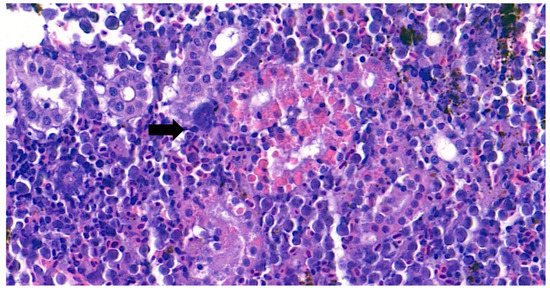

Furthermore, the infiltration of diverse immunocytes, including lymphocytes and macrophages, was observed surrounding the tubule (Figure 2). In addition, signs of bacteremia along the degenerated tubule (Figure 3) were observed with cellular debris surrounding the tubules (Figure 2). Similar signs were also observed in the liver of the diseased fish. A few necrotizing areas with infiltration of macrophages and lymphocytes and vacuolation of hepatic cells was observed (Figure 4a,b).

Figure 4.

(a). Representative image of hematoxylin and eosin-stained tissue section showing focal necrotizing areas in the liver of the diseased fish. Cellular vacuolation can be observed around the lesion. (Bar indicating 10 µm). (b). Representative image of hematoxylin and eosin-stained tissue section showing infiltration of macrophages and lymphocytes with signs of bacteremia (arrow) in the liver of the diseased fish. 4 (c). Negative fish group liver image stained with hematoxylin and eosin. (Bar indicating 10 µm).

Similar severity of lesion formation was not observed in the spleen, which suggested the liver and kidney as the target organs of the bacteria. Signs of bacteremia and cellular degeneration were observed in the liver and kidney, but not in the spleen. Therefore, the cause of the mortality of fish can be speculated as bacteremia.